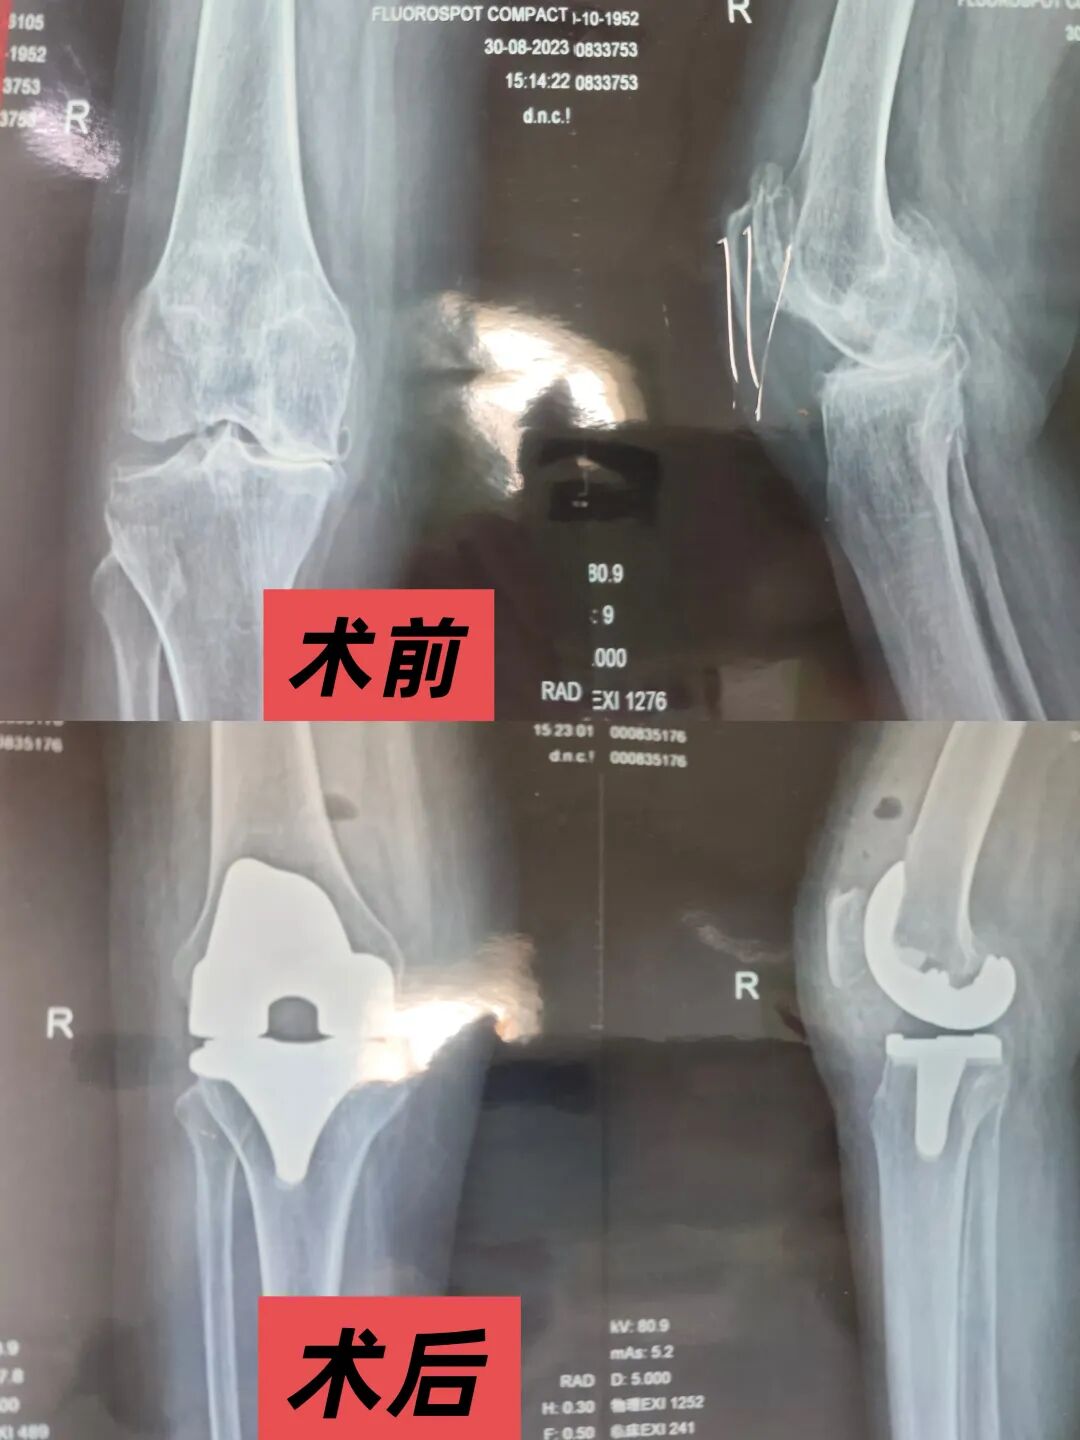

据悉,林先生因长期从事重体力劳动,双膝关节骨性关节炎逐年加重,关节畸形、疼痛剧烈,日常行走仅能维持数百米。2024年11月,骨科团队为其制定个性化方案,先行左侧膝关节置换术。术中精准截骨、软组织平衡技术,结合个性化假体匹配,最大限度保留关节功能;术后通过多模式镇痛与个性化康复训练,帮助患者3天即可下床活动。

今年10月,基于左侧手术的成功经验,团队为林先生实施右侧膝关节置换术。两次手术均采用“快速康复(ERAS)理念”,通过优化麻醉管理、减少术中出血、控制术后炎症等措施,将传统手术恢复周期缩短近一半。如今复查显示,林先生双膝关节活动度完全正常,已能独立完成上下楼梯、长距离行走等动作,彻底告别了“疼痛缠身、举步维艰”的日子。11月24日林先生手持一面写有“医术精湛品德高,惠及患者暖民心”的锦旗,专程来到金台医院骨科住院部,向为他成功实施双膝关节置换术的医疗团队表达感激之情。